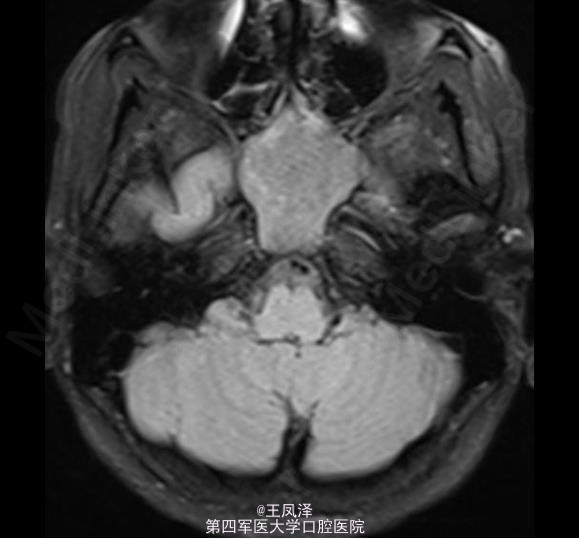

蝶窦粘液囊肿一例

女性,20 岁,在 18 个月大时诊断为自闭症和智力迟钝,目前发生多次抽搐现象,可能为癫痫发作。